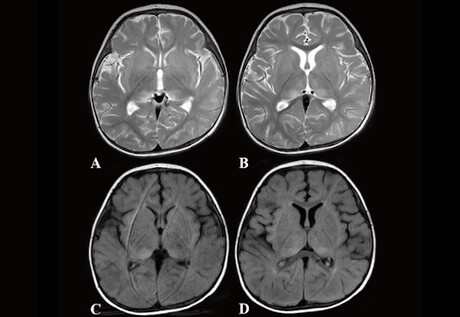

Led by Hiroshima University, researchers detected two novel IRAK4 mutations — c.29_30delAT (p.Y10Cfs*9) and c.35G>C (p.R12P) — in a 10-month-old boy with anti-N-methyl-d-aspartate receptor (anti-NMDAR) encephalitis and human herpesvirus 6 (HHV6) reactivation. The p.Y10Cfs*9 and p.R12P variations were inherited from his father and mother, respectively. The research team found the mutations by using whole exome sequencing (WES), a method used to exhaustively examine the DNA for genetic disorders.

Anti-NMDAR encephalitis, an inflammation of the brain, happens when the immune system attacks a vital brain receptor, causing psychiatric symptoms, involuntary movement, seizures, autonomic dysfunction and central hypoventilation. It typically occurs in adult females suffering from ovarian tumour — only a few cases of anti-NMDAR encephalitis have been so far reported in infants — but the researchers suspect that reactivation of HHV6 may have induced brain damage that triggered the production of anti-NMDAR antibodies.